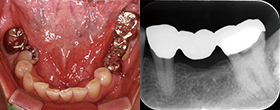

EdgeSequel Sapphire™を使用した臨床例

Case1 湾曲根管

Case2 直線根管